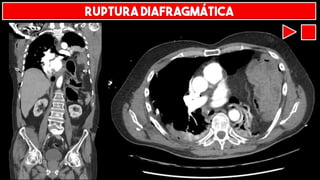

RUPTURA DIAFRAGMÁTICA

RUPTURA

DIAFRAGMÁTICA

HÉRNIA DIAFRAGMÁTICA